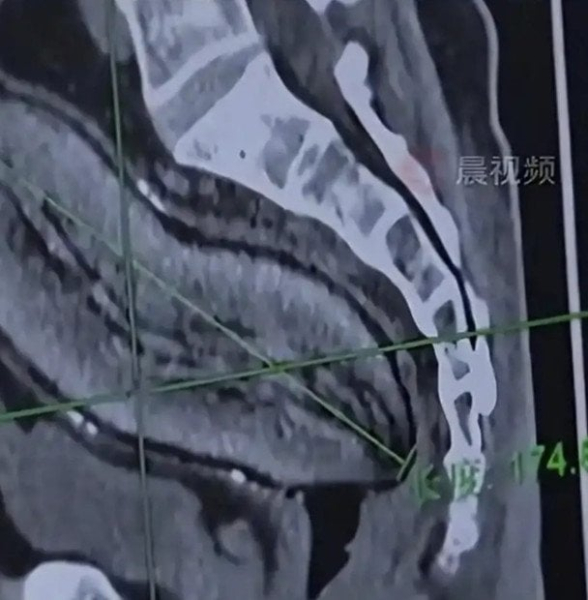

61-річний чоловік помістив коренеплід довжиною близько 17 сантиметрів пізно ввечері — приблизно о 23:00. Як зазначається, зробив він це «від нудьги», після чого ліг спати.

Заступник директора відділення проктології та дерматології лікарні доктор Сю Гуолінь повідомив, що предмет мав приблизно 17 см у довжину та майже 7 см у ширину.